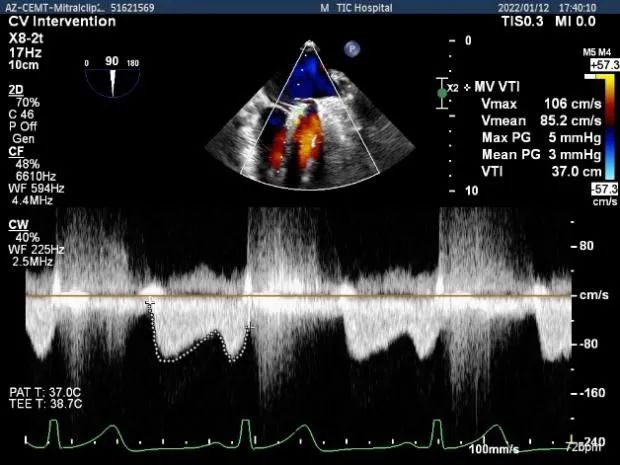

第二个夹子放置侯二尖瓣口平均跨瓣压差:3mmHg

肺静脉血流频谱完全恢复正向

x-plane验证前后叶抓捕后跳跃征明显

3D-view验证两个夹子位置稳定,排列紧密

3D-Color-view验证微少量残余返流